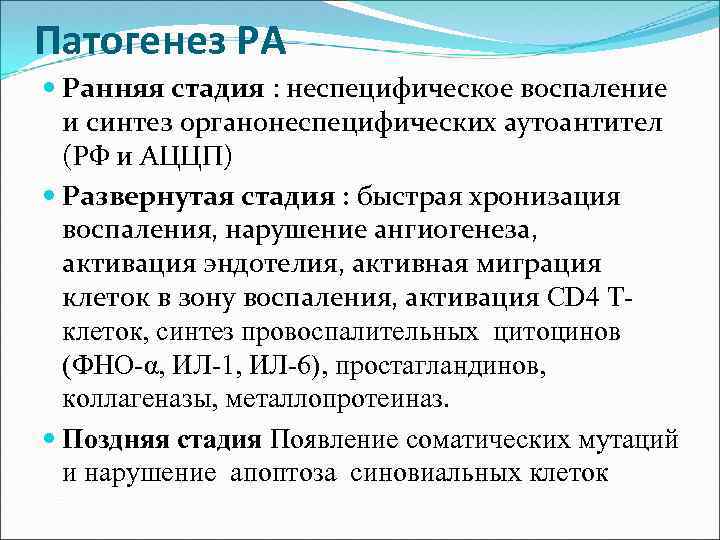

Патогенез РА Ранняя стадия : неспецифическое воспаление и синтез органонеспецифических аутоантител (РФ и АЦЦП) Развернутая стадия : быстрая хронизация воспаления, нарушение ангиогенеза, активация эндотелия, активная миграция клеток в зону воспаления, активация CD 4 Тклеток, синтез провоспалительных цитоцинов (ФНО-α, ИЛ-1, ИЛ-6), простагландинов, коллагеназы, металлопротеиназ. Поздняя стадия Появление соматических мутаций и нарушение апоптоза синовиальных клеток

Патогенез РА Ранняя стадия : неспецифическое воспаление и синтез органонеспецифических аутоантител (РФ и АЦЦП) Развернутая стадия : быстрая хронизация воспаления, нарушение ангиогенеза, активация эндотелия, активная миграция клеток в зону воспаления, активация CD 4 Тклеток, синтез провоспалительных цитоцинов (ФНО-α, ИЛ-1, ИЛ-6), простагландинов, коллагеназы, металлопротеиназ. Поздняя стадия Появление соматических мутаций и нарушение апоптоза синовиальных клеток